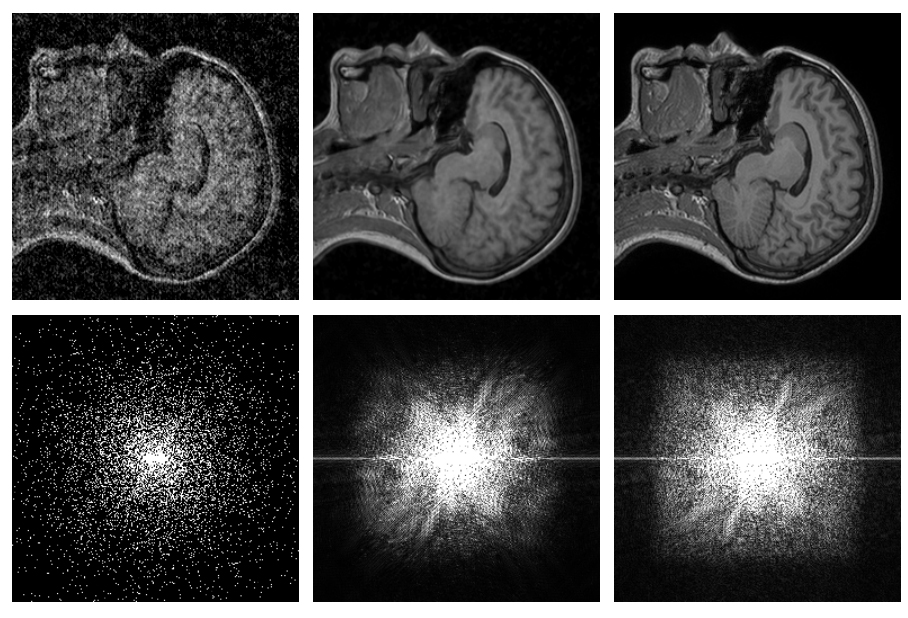

英伟达通过人工智能技术对照片进行降噪提高清晰度英伟达研究院和麻省理工学院的研究团队正在通过人工智能技术将照片上的噪点移除以便提高照片的清晰度。 尽管现在通过某些软件已经可以修复照片上的…2018年7月17日 15:1823.33W